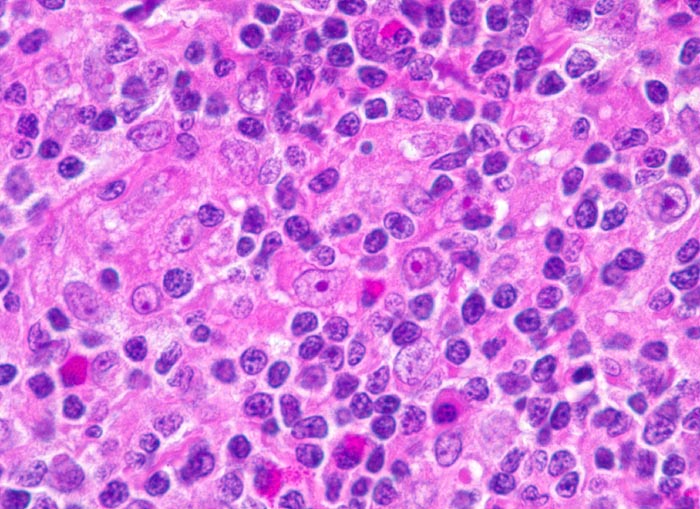

Das Zellbild ist bunt und umfasst Lymphozyten, Plasmazellen, eosinophile Granulozyten und einzeln im reaktiven Infiltrat liegende Tumorzellen. Die Tumorzellen sind einkernig (Hodgkin Zelle) oder mehrkernig (Reed-Sternbergzellen) und enthalten einen sehr grossen Nukleolus. Die Tumorzellen sind immunzytochemisch positiv für CD15 und CD30. Nodulär sklerosierender und gemischtzelliger Subtyp des Hodgkin Lymphoms sind zytologisch nicht sicher zu unterscheiden.

Gezeigt werden eine noduläre Sklerose und zwei Hodgkin Lymphome vom Mischzelltyp.